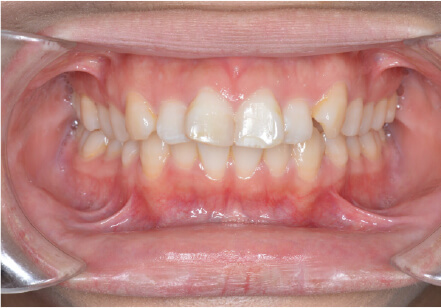

9歳

女性

マイオスマイルからの移行

上11捻転、上33スペース不足、インビザで歯列矯正

全額アライナー矯正 クリアコレクト

リンガルアーチ使用

痛み・歯根吸収・歯肉退縮・虫歯・後戻り

(マウスピース矯正のみ)440,000円+220,000円 月々27,500円、9ヶ月+myo1年10ヶ